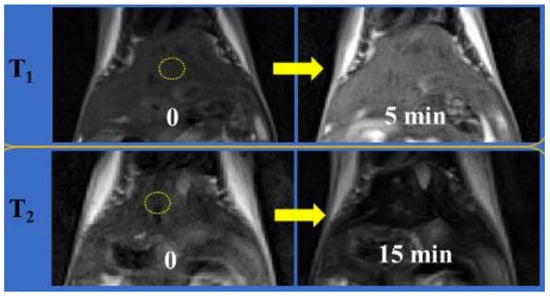

- Shin, T.-H.; Choi, J.-s.; Yun, S.; Kim, I.-S.; Song, H.-T.; Kim, Y.; Park, K.I.; Cheon, J. T1 and T2 dual-mode MRI contrast agent for enhancing accuracy by engineered nanomaterials. ACS Nano 2014, 8, 3393–3401. [Google Scholar] [CrossRef]